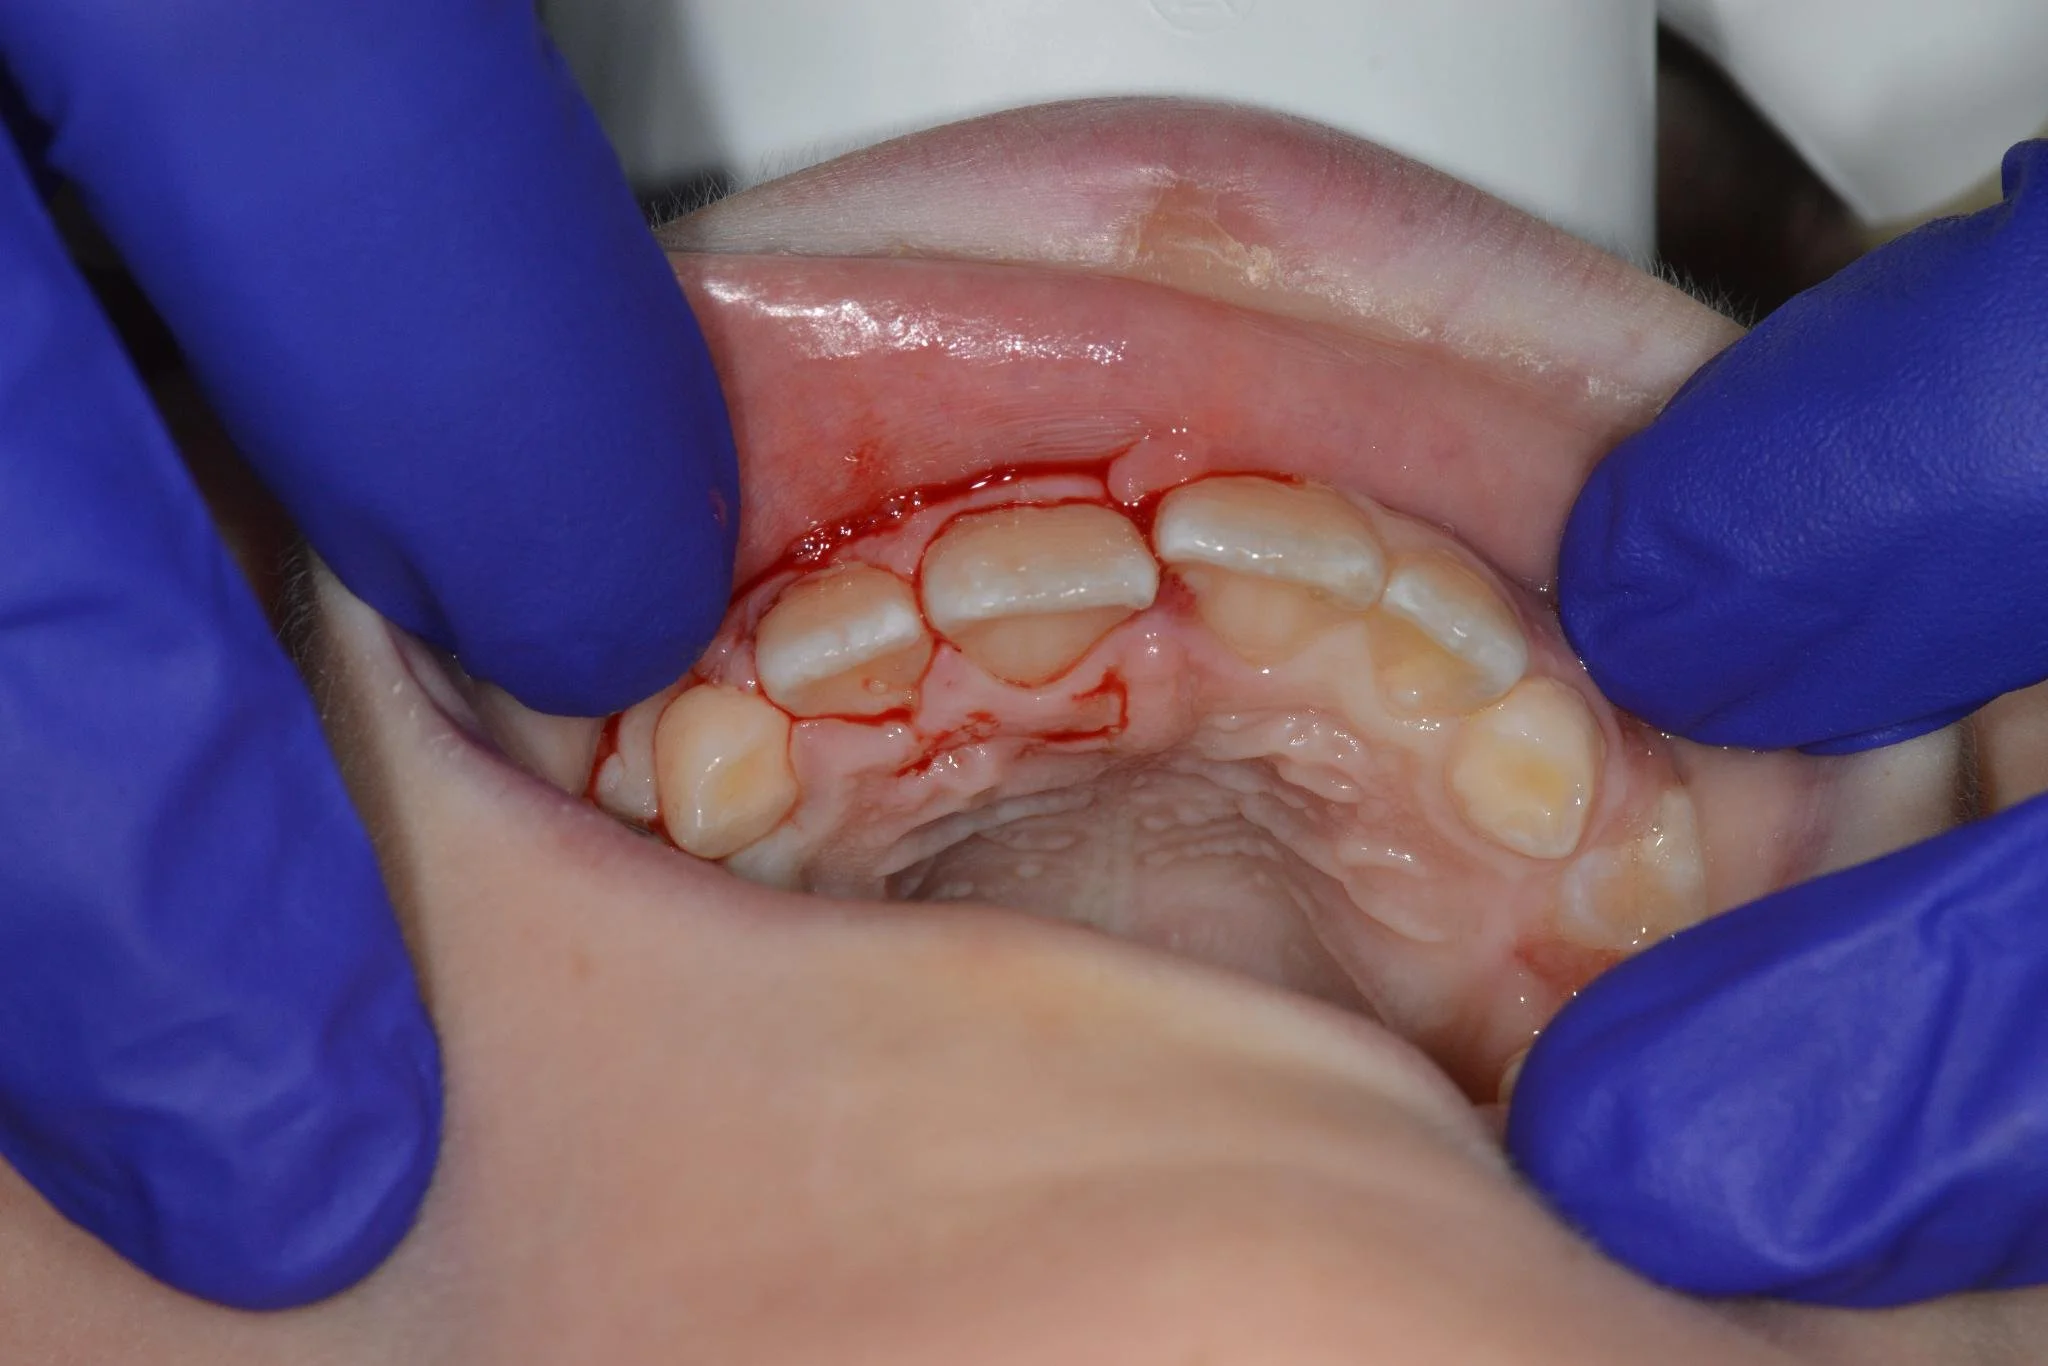

4. Avulsed (Knocked-Out) Tooth Reimplantation

If a permanent tooth is knocked out:

• Immediate reimplantation and splinting are performed

• Antibiotics and follow-up RCT if necessary

(Primary teeth are not reimplanted.)

3. Tooth Repositioning & Splinting

For displaced or loosened teeth, we offer:

• Gentle repositioning under local anesthesia

• Splinting for stabilization (2–4 weeks)

• Regular vitality testing and follow-up